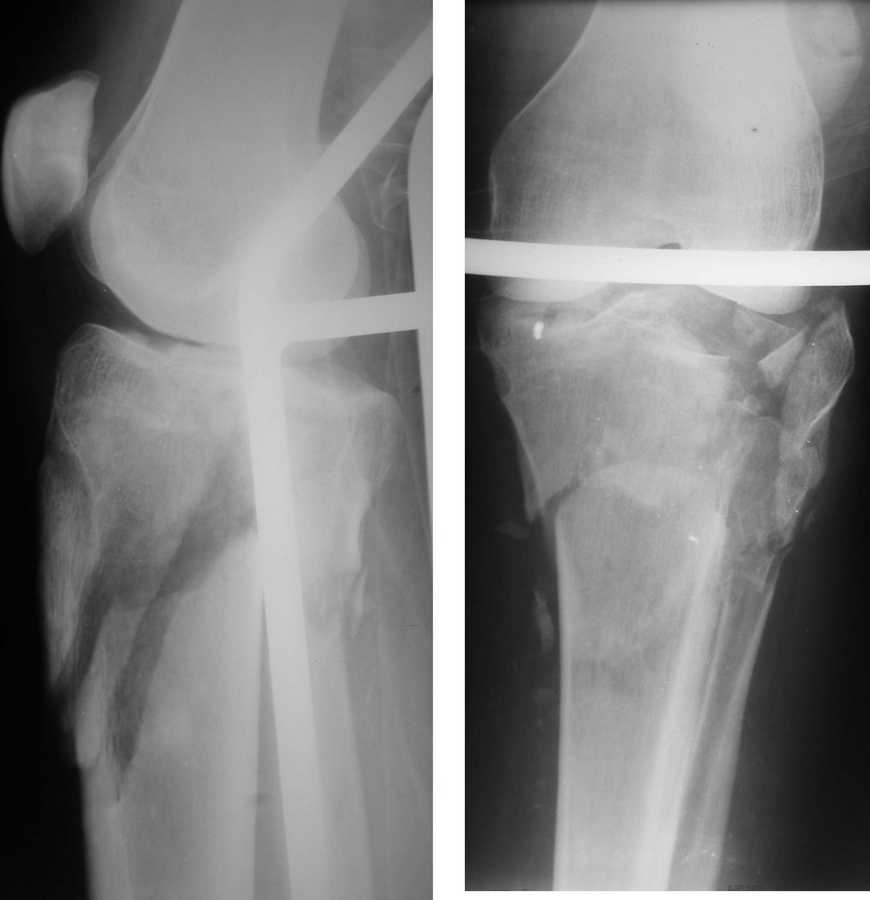

Саша, а в чем конкретно неясность? Надо полагать, вопрос не про общие принципы лечения переломов типа Schatzker VI или C3 по классификации AO, которые можно найти в любом руководстве?

Состояние мягких тканей оказалось принципиальным в разработке плана операции.

Очаг некроза 4 на 5 см по передней поверхности голени не оставил никакого варианта кроме внешнего остеосинтеза.

Но решили делать в 2 этапа. Первый - восстановить ось и дать костной крошке в проксимальном отделе консолидироваться.

Второй - собственно артродез.

Но по результатам первого этапа думаем дать пациенту попользоваться ногой. А там посмотрим.